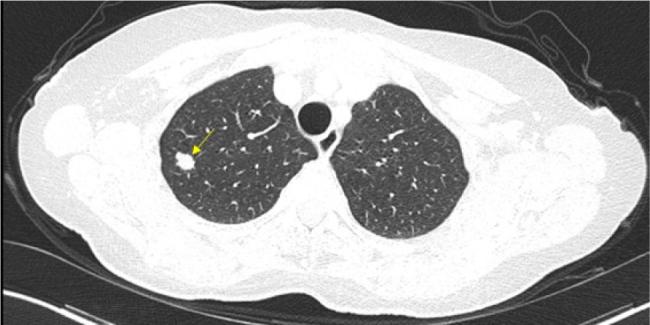

尿路上皮癌是全球最常被诊断出的癌症类型之一,尽管治疗取得了进展,但在转移阶段它仍然是一种致命疾病。由于其程序性细胞死亡配体1蛋白表达水平高,它与对免疫检查点抑制剂的反应增加有关。在过去几年中,转移性尿路上皮癌一线治疗的金标准一直是铂类化疗,以及对无进展肿瘤进行阿维鲁单抗(一种PD - 1抑制剂)维持治疗。在EV - 302研究显示出显著疗效后,指南最近进行了修订,将恩沃利单抗联合帕博利珠单抗纳入该情况下的新治疗标准。尽管有新的建议,但在一些国家,这种联合治疗仍有待批准。此外,对于不符合恩沃利单抗联合帕博利珠单抗治疗条件的患者,铂类化疗后进行阿维鲁单抗维持治疗仍然是首选的治疗方案。本报告介绍了一名被诊断为转移性尿路上皮癌的女性,在接受顺铂和吉西他滨化疗以及阿维鲁单抗维持治疗后,组织学证实完全缓解,这种情况在文献中仅有少数病例报道。